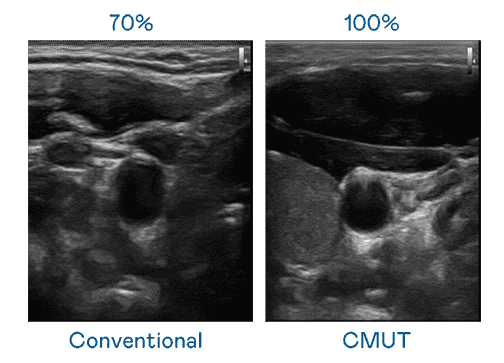

CMUT 技术是一种用电容式微机电元件来产生超音波讯号的技术。。。与传统 PZT 压电式技术相比,,CMUT 频宽增加 30%,,,更宽频的超音波讯号让影像解析度大幅提升,,,,是实现高影像品质医疗超音波扫描、、、、促进精准医疗发展的关键技术。。

大频宽带来超清晰影像

超音波影像的解析度高低,,,,首先取决于探头能发出的讯号频宽。。口袋牛店 CMUT 可提供高清晰的超音波讯号,,提供高频宽、、、高灵敏度、、、、影像纹理细节更高的超音波影像,,协助医护人员缩短影像判读时间及利用精准的医疗影像进行诊断。。。